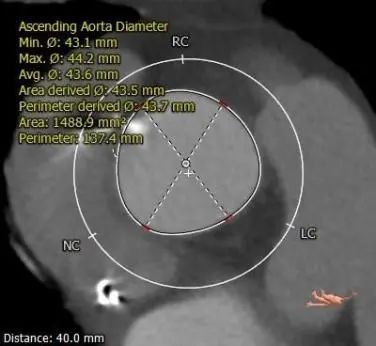

主动脉根部测量

瓣上测量

3.推荐22mm球囊预扩,根据球扩后腰征决定AV26还是AV29瓣膜,瓣环下2mm定位释放,建议释放后调整至右前斜足位 RAO 6 CRA 35 左右进一步确定人工瓣膜展开形态。

4.接近横位心,升主动脉严重扩张扭曲,输送器及球囊跨瓣难度高,必要时Snare辅助。